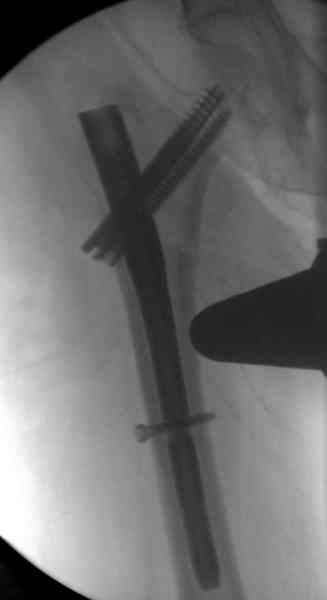

В общем, сделали. См. приложение.

Длина и из-за этого ось получились не совсем такие, как хотелось бы, все-таки срок после той операции уже 6 недель. Может быть, стоило провести дистракцию аппаратом неделю-другую. Заранее спасибо за комментарии и критику.